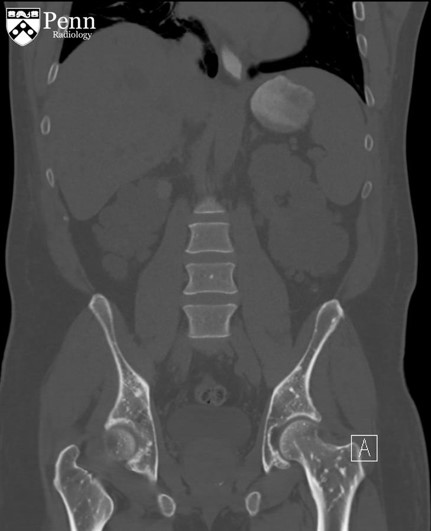

病史 男性,52岁,主诉腹部疼痛伴不明原因菌血症;患者有慢性肾病史。

腹盆CT图像如下

1.CT显示骨密度病变呈不均匀分布?(单选)

2.骨病变有大范围转移?(单选)

4.下面哪个是骨病变最可能的病因?(单选) 转移性肾细胞肾癌 转移性前列腺癌 骨斑点症 纹状骨病 肥大细胞增多症

5.以上骨病变的异常发生在骨的哪个部位?(单选)